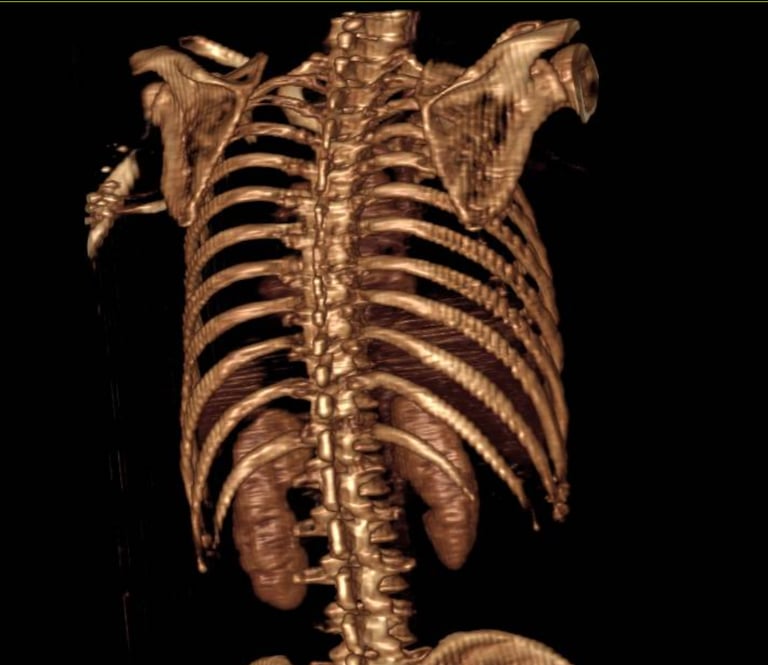

Tumores de la columna torácica y de los nervios o la medula espinal.

Escoliosis idiopática juvenil.

Escoliosis degenerativa del adulto mayor.

Columna torácica.